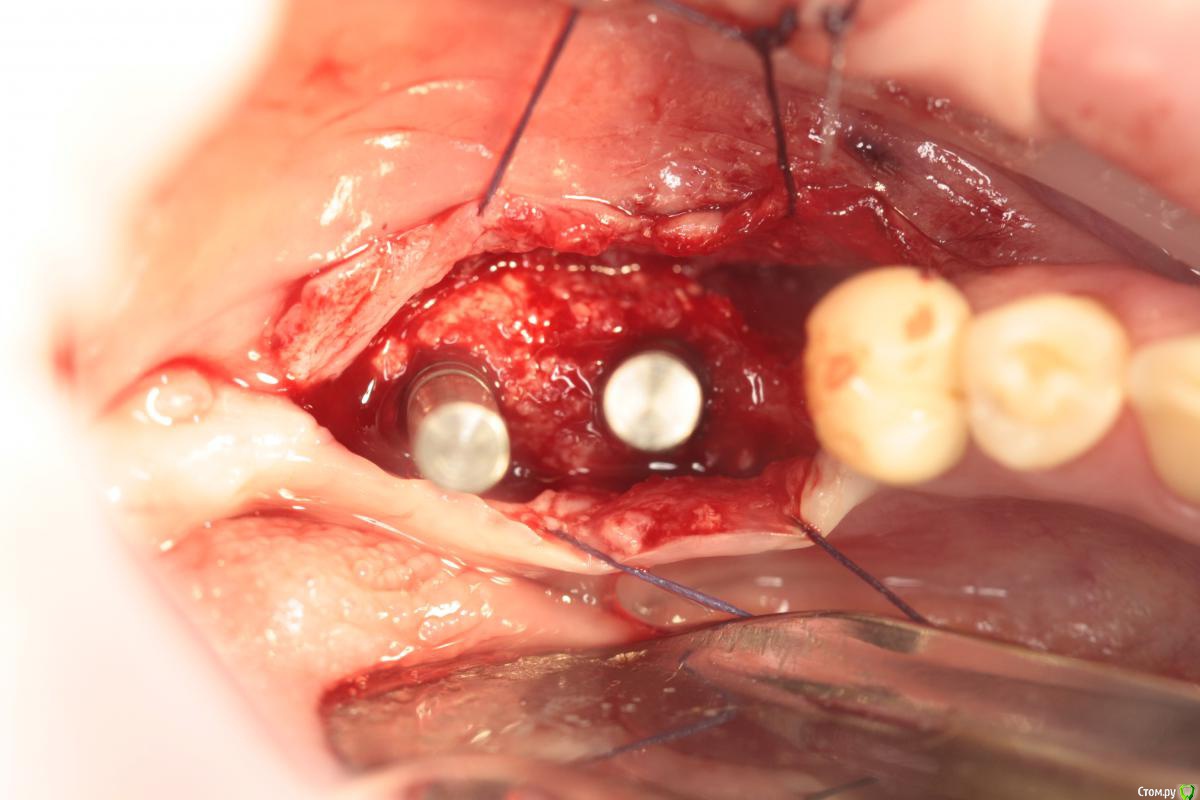

Endorphin Опубликовано 11 августа, 2015 Поделиться Опубликовано 11 августа, 2015 Добрый день, Коллеги!Хочу с Вашей помощью принять оптимальное решение по выходу из сложившейся ситуации.23.06.2015 пациентке проведена аугментация в 4 сегменте. Biooss L+ауто 50:50. Графт перекрыт мембраной biotec с титановым усилением, мембрана перекрыта отжатыми сгустками prp. Ушивание без натяжения (турбомобилизировал по Mane), матрацный и обвивной шов. 27.06 - швы состоятельны, без особенностей04.07 - снятие швов08.07 - при осмотре обратил внимание на незначительный участок оголения мембраны язычно(на фото)решил наблюдать, в надежде что затянется.Пациентка пропала на месяц.11.8.15 - Жалоб нет. Признаков воспаления нет. Обширное оголение мембраны (примерно 1 см2).Принял решение мембрану завтра удалить. Из своих косяков могу выделить слишком дистальное расположение мембраны.Причины неприятности думаю кроются в мембране - у коллеги она очень нередко ведет себя так же. На ощупь она как полиэтилен и, в отличие от cytoplast и goretex (если не ошибаюсь) не имеет пор и полностью изолирует слизистую от кости. Вопрос - как быть с дефектом мягких тканей? Из вариантов - попытаться ушить наглухо или сделать каппу (или защитную пластинку, как в кейсе Большого Зеленого) с пространством для роста грануляций. Склоняюсь ко второму варианту. Буду признателен за любые комментарии. 1 Ссылка на комментарий

Endorphin Опубликовано 9 сентября, 2015 Автор Поделиться Опубликовано 9 сентября, 2015 (изменено) Продолжение истории.По Вашим советам мембрану оставил, наблюдал пациентку раз в неделю. Отмечалась тенденция к росту области прорезывания, в связи с чем было решено мембрану удалить ( не хотелось дожидаться оголения края мембраны). На момент удаления мембране исполнилось 3 месяца. Анестезия, разрез по гребню примерно на 3/4 длины мембраны. Мембрана и пины ушли без боя, в области прорезывания обнаружился желеобразнный фибрин. Там, где над мембраной сохранилась слизистая, на месте графта образовалась твердая ткань, надо полагать, выросла кость. Иммобилизировать, ушивать наглухо, подкладывать сст не стал. Наложил сближающие швы, швы на разрез. Прошла неделя. Через 1.5 - 2 месяца планирую КТ и если это действительно была кость, то имплантацию с сст. Спасибо всем, кто отговаривал меня удалять мембрану . Изменено 9 сентября, 2015 пользователем Endorphin 13 Ссылка на комментарий

Endorphin Опубликовано 30 января, 2016 Автор Поделиться Опубликовано 30 января, 2016 Сделайте фото когда ставить будете, очень интересноСделал.Результат превзошел ожидания. Из-за изначально неправильного расположения мембраны и графта, "ширина" начинается лишь отступя 6.5 мм от шейки 45, так что центр платформы дистализирован для моляра (8.5мм когда хочется 6мм). Качество фото так себе, но суть, думаю, ясна - кость наросла в достаточном объеме и качестве, торк > 45. Обязательно ССТ под швы. Еще раз всем спасибо! 1 Ссылка на комментарий